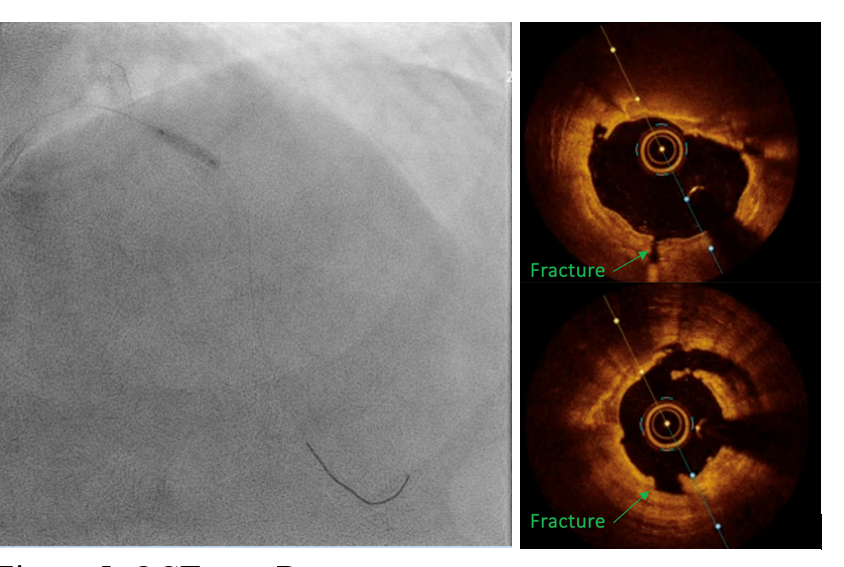

PCIof the LAD was performed via femoral access using a BL 3.5/7F guiding catheter.A Runthrough Hypercoat wire was advanced distally without difficulty. The OCTcatheter failed to cross the lesion, and a 2.5 ¡¿ 15 mm scoring balloon couldnot pass the mid LAD. A microcatheter was inserted, and the wire was exchangedfor a Rotawire. Rotational atherectomy was performed using a 1.25 mm burr withshort, gentle pecking runs at 180,000 rpm, followed by upsizing to a 1.5 mmburr for three runs at 200,000 (2 times) and 160,000 rpm. The burr advancedsmoothly with improved tactile feedback, suggesting successful plaquemodification. The wire was exchanged back to a Runthrough, and OCT (DragonflyOPTIS) imaging showed an MLA of 1.43 mm©÷ at mid LAD with severe 360¡Æ calcification(0.9 mm thick, 41 mm long) and a napkin-ring pattern. A 2.5 ¡¿ 15 mm cuttingballoon was used with multiple 14–18 atm inflations, producing a visible¡°crack¡± in the calcified cap. Angiography and repeat OCT confirmed the calciumfracture. A 3.0 ¡¿ 46 mm DES was deployed from the ostial to distal LAD at 14atm and post-dilated with a 3.5 mm NC balloon proximally. Final angiographyshowed TIMI 3 flow. OCT demonstrated excellent stent expansion (MSA 7.78 mm©÷proximal, 3.28 mm©÷ distal) without dissection and with 107% stent expansion.